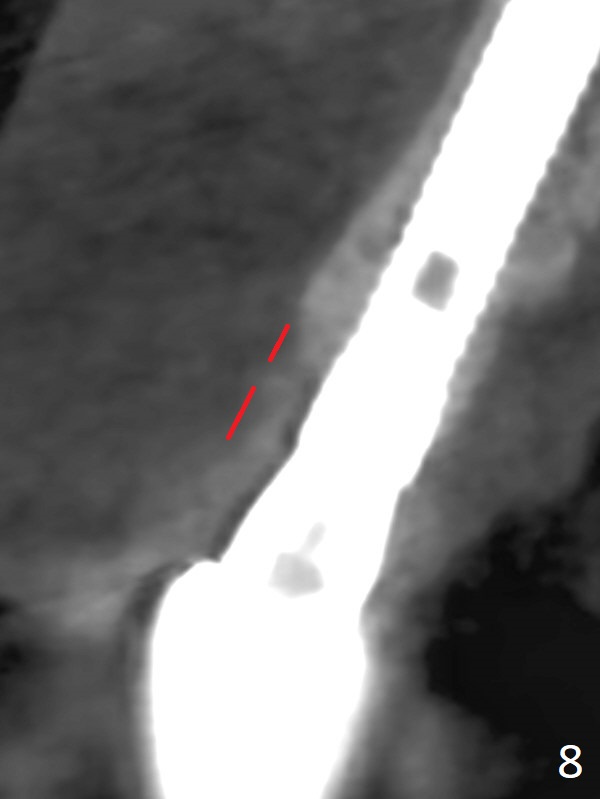

The patient returns because of purulent exudate from the buccal fistula (Fig.1 *) 1 year 9 months postop (1 year 3 months post cementation). Preop CT shows buccal thread exposure (Fig.2 arrowheads). To prevent postop gingival recession, a semilunar incision is made between the fistula and the gingival margin (Fig.3). After removal of granulation tissue (Fig.4), allograft in sticky bone form is packed (Fig.5). Following placement of PRF membrane and 6-month collagen membrane, the wound is closed (Fig.6). Since the implant (Fig.7 I) thread exposure is within bone (B) boundary (Fig.8 red dashed line), bone graft with PRF should be able to take care of periimplantitis (A: abutment). To prevent periimplantitis in similar situation, the immediate implant should be placed deep (not necessarily long, 18 mm) and narrower (3.5 mm instead of 3.8 mm). The defective buccal plate should be repaired with sticky bone and collagen membrane with incision if necessary. The wound does not dehisce 1 week postop (Fig.9) or 3 weeks postop (Fig.10, immediately post suture removal). Although bone graft seems to stay in place 6 months postop (Fig.11,12), the patient complains of bone graft expulsion sometimes. The buccal gingiva has deficiency (Fig.13). To fix it, make a remote incision (Fig.14 black line) and dissect before gingiva graft (Fig.15 dashed line). After removal of crown/abutment, the sinus track and implant surface are treated with Waterlase. A shorter cuff abutment is placed (4.5x5(4 to 3) mm) with a new provisional. The patient feels better with reduced sinus track 2 weeks postop (Fig.16).